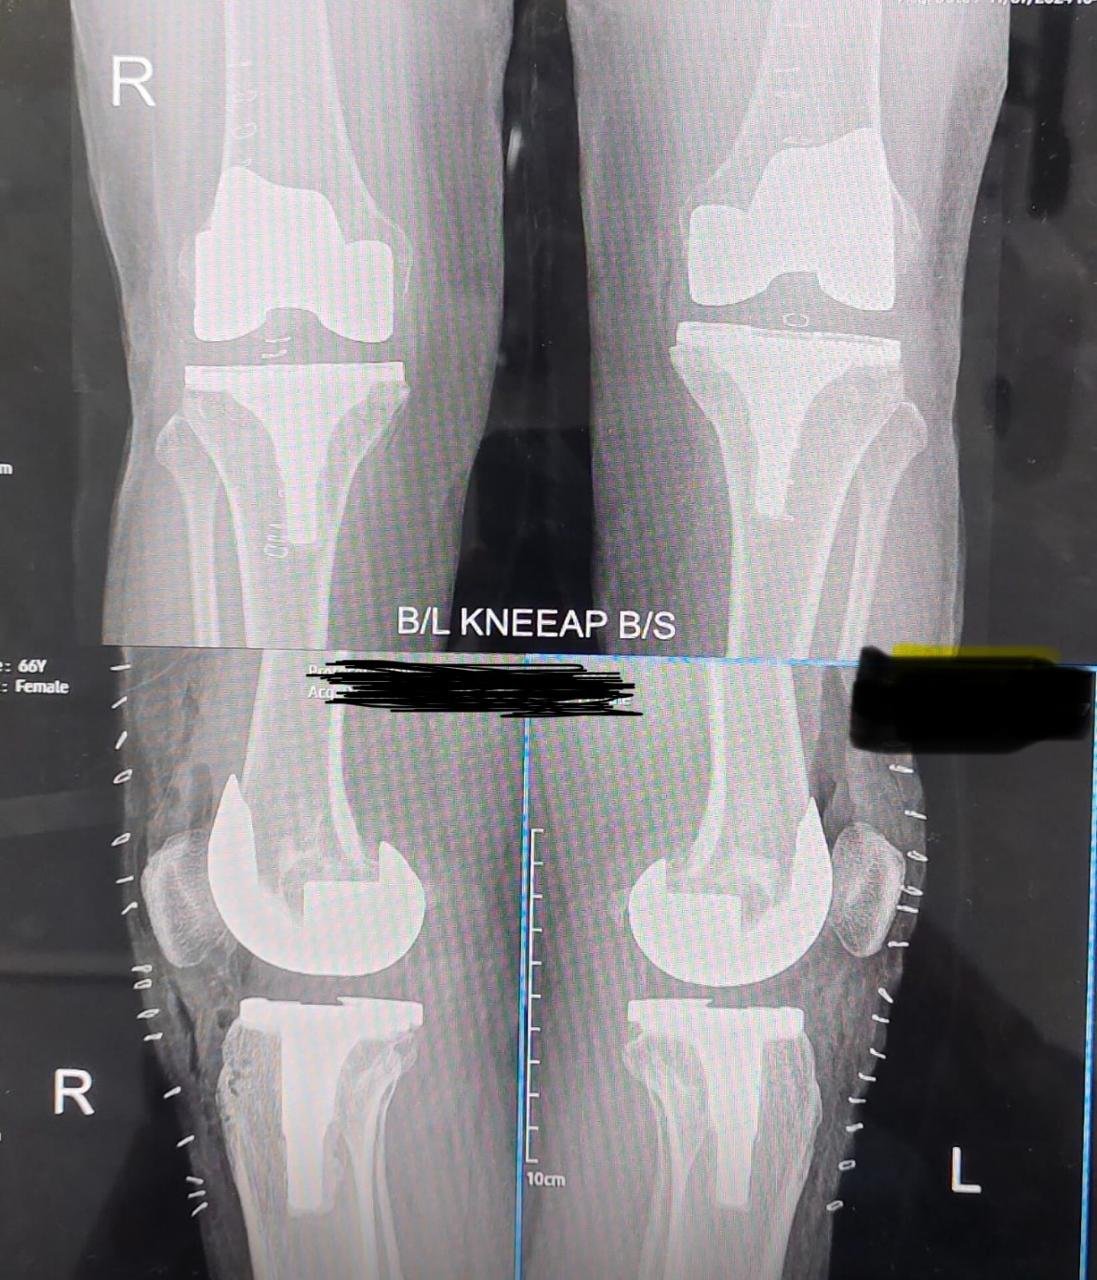

Total Knee Replacement

Total Knee Replacement is a highly effective surgical procedure designed to relieve severe knee pain and restore mobility in patients suffering from advanced arthritis or joint damage. The procedure involves replacing the damaged knee surfaces with high-quality prosthetic components that replicate natural joint movement. With modern implants, advanced surgical techniques, and expert postoperative care, patients can achieve long-term pain relief, improved stability, and an enhanced quality of life. This treatment is recommended when non-surgical therapies are no longer sufficient to provide comfort or functional improvement. With modern implants, advanced surgical techniques, and expert postoperative care, patients can achieve long-term pain relief, improved stability, and an enhanced quality of life. This treatment is recommended when non-surgical therapies are no longer sufficient to provide comfort or functional improvement.